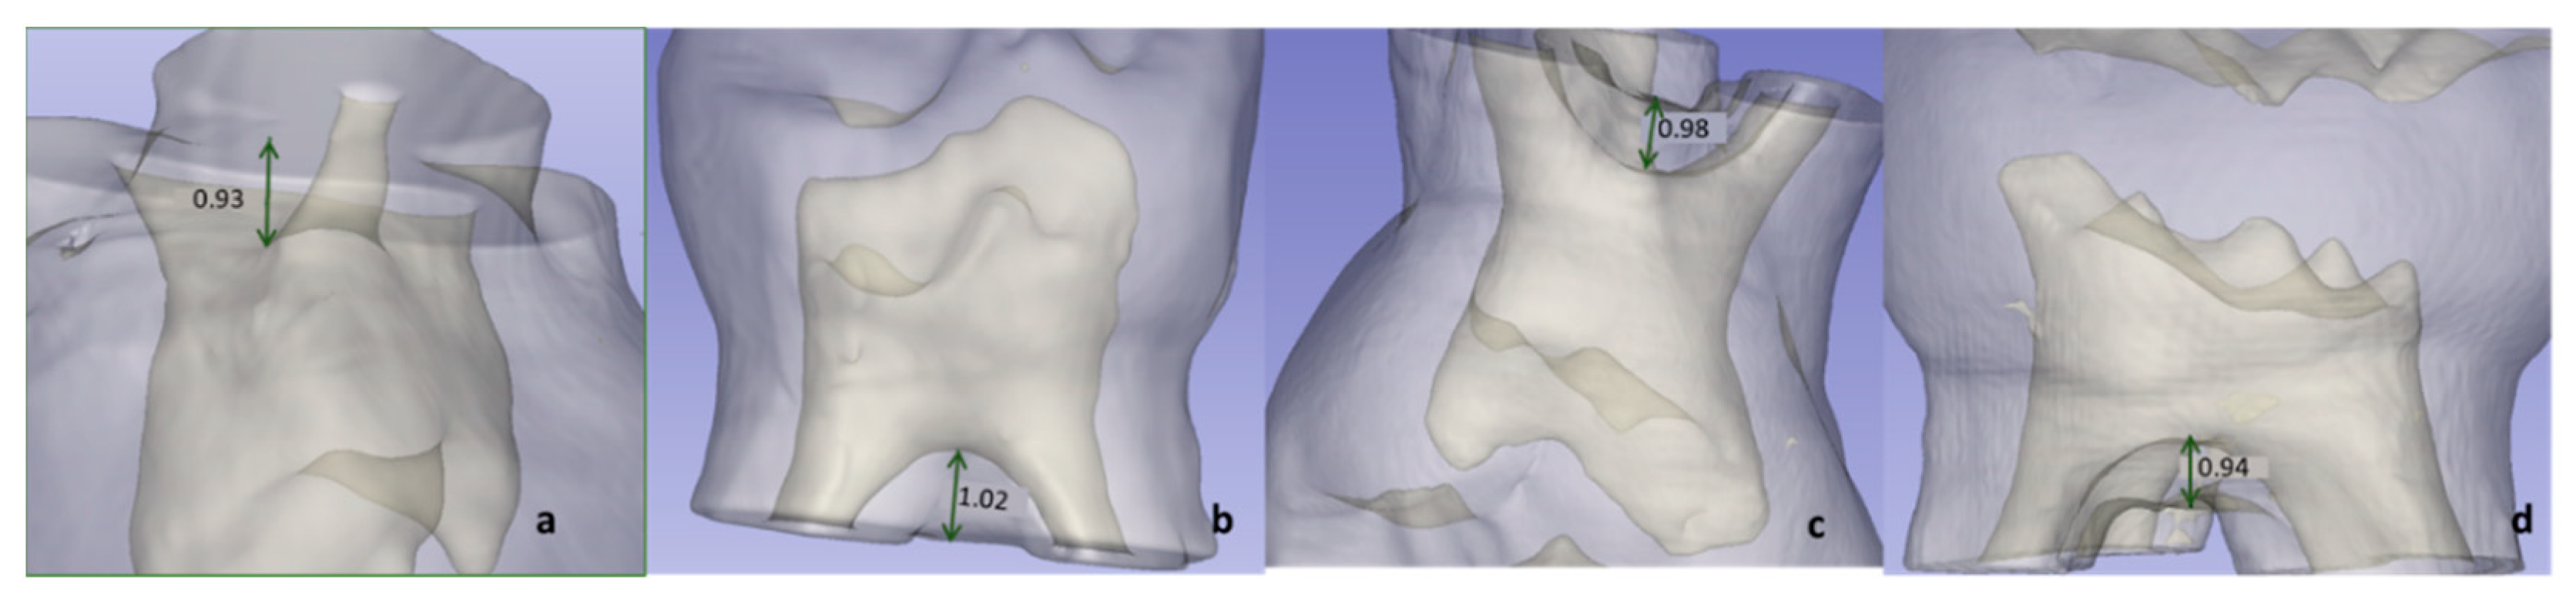

2.4.2. Distance between Pulp Chamber Floor and Furcation (FD)